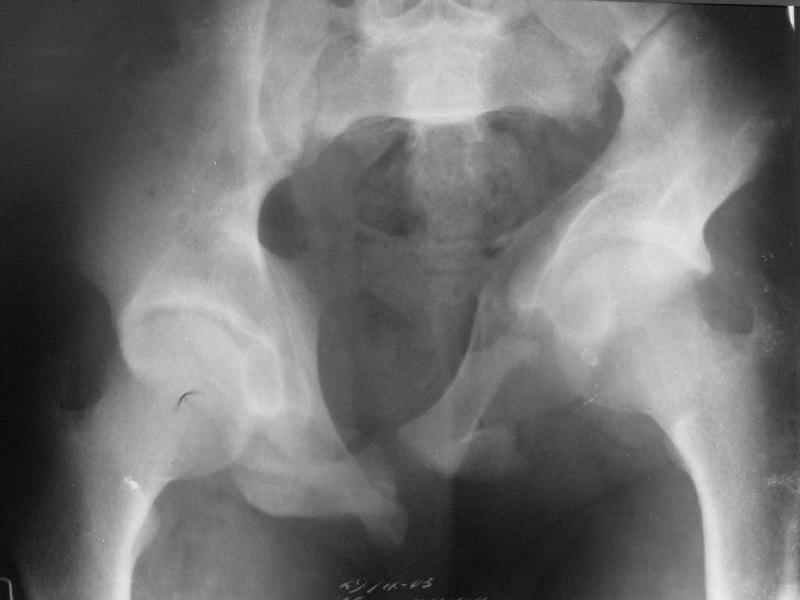

Ув. коллеги, к нам поступил молодой человек 17 лет. Травма в июле 2005- ДТП, т.е. 3 мес назад. Лечился консервативно в "гамаке" 1,5 мес., затем ходьба с костылями без опоры на левую нижнюю конечность, начал на нее опираться 1 нед назад.

В настоящее время имеется укорочение порядка 4-5 см, выраженная хромота, передвигается с одним костылем. Кроме того беспокоят боли в пояснично-крестцовой области при ходьбе, неудобство при сидении, невозможность лежать на спине "на жестком", а также на левом боку (субъект худощавый, боль в области крыла) хромота, длительное пребывание на ногах невозможно.